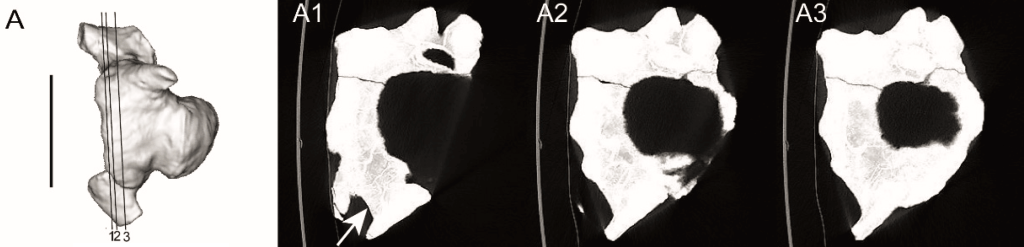

MAU-Pv-LI-601 et MAU-Pv-LJ-472/1 présentent toutes deux des signes indiquant la présence d’une pathologie. Elles montrent toutes deux des signes d’une réaction périostée, c’est-à-dire une sur-ossification de l’os, causée par une pathologie. Les deux vertèbres présentent également des zones à la structure rugueuse et perforée, qui témoigne d’une possible infection. En plus de cela, MAU-Pv-LI-601 est atteinte d’une ankylose au niveau du chevron. Pour avoir une meilleure idée des pathologies atteignant MAU-Pv-LI-601 et MAU-Pv-LJ-472/1, Cruzado-Caballero et ses collègues les ont passées au scanner CT. Ces scans CT confirment leurs observations externes et permettent de constater l’absence de fractures sur ces deux vertèbres.

A partir de ces observations, Cruzado-Caballero et ses collègues ont pu donner un diagnostic des pathologies atteignant MAU-Pv-LI-601 et MAU-Pv-LJ-472/1. Selon eux, la vertèbre MAU-Pv-LI-601 est atteinte d’une spondylarthropathie. Ce terme désigne un ensemble de rhumatismes inflammatoires, c’est-à-dire des pathologies articulaires. Le peu de données disponibles ne permet pas de préciser quel type de spondylarthropathie affectait MAU-Pv-LI-601. Cette pathologie n’a pas causé de douleur au spécimen, et n’a pas non plus atteint sa mobilité.

Cruzado-Caballero et ses collègues déclarent que la vertèbre MAU-Pv-LJ-472/1 était atteinte d’une infection pyogène, c’est-à-dire productrice de pus. Ils affirment que cette infection était très probablement une ostéomyélite, causée par des microorganismes suite à l’infection d’une plaie aux tissus mous de la queue. Cette pathologie a pu être douloureuse, et restreindre la mobilité de la partie postérieure de la queue de MAU-Pv-LJ-472/1.